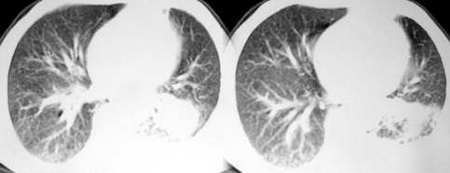

以下是引用sdqzwyx在2005-11-7 19:59:00的发言:[br]双肺弥漫大小不等的粟粒状结节影;肺纹理走行失去自然,粗细不均,边缘不规则,小叶间隔增厚;左上肺示不规则形致密影,从斑块边缘向周围伸出长短不一的致密索条影,临近的血管、支气管和叶间胸膜等结构受牵拉移位;左下肺示不规则团块状影,其内示空洞,洞内壁尚光整,左侧胸腔积液。右肺下叶背段亦示部分病灶融合。双肺可见局限性肺气肿。[br]诊断:结合病史符合三期矽肺表现(少数矽肺纤维斑块内可以形成空洞,一般认为是斑块中央感染引起坏死所致)但尘肺病人易合并肺结核,诊断可为三期+tb。所以此病人应进一步检查是否合并结核。